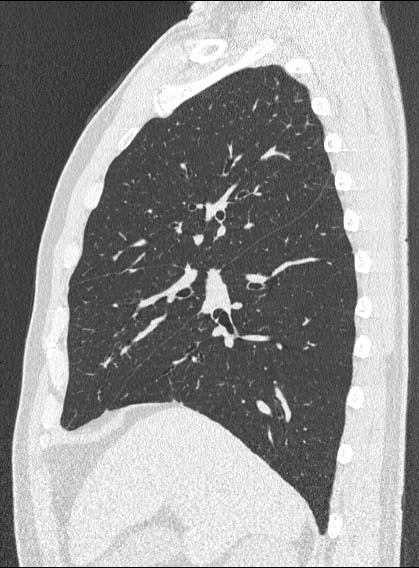

Advanced Aquilion Prototype (8-row)

Clinical example #2

Normal Chest

0.5mmx8, pitch 10,